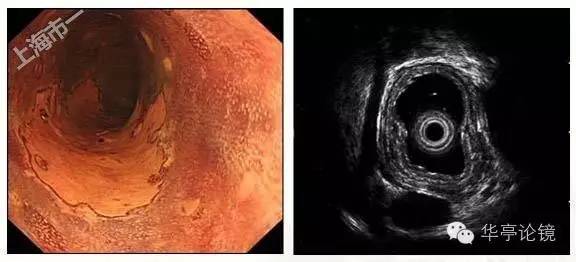

白光内镜:距门齿25-28cm处见病变区粘膜发红,表面粗糙,分支血管网消失,病变约占环周面积3/4,与周围正常粘膜分界清晰。卢戈氏碘染色见病变处粘膜脱染。

ME-NBI内镜:病变处见背景着色,IPCL呈V1-V3型改变,预测病变深度可达m3-sm1。

2016年7月12日于我内镜中心行食管早癌ESD术,粘膜下注射靛胭脂-甘油果糖溶液,见病灶不完全隆起,非抬举征可疑(+),将病灶周边完整剥离切除,直至固有肌层,切除过程中间病灶部分与固有肌层粘连。

ESD术切除标本见下图。

完整切除组织送检,20160719病理:(5X2.5cm,厚0.3cM,灰白组织一块):食管粘膜鳞状细胞上皮高级别上皮内瘤变,粘膜内癌形成,局部浸润至粘膜下层,病变肉眼范围约4X1.5cm,局灶瘤变鳞状上皮下查见少量腺癌成分,腺癌浸润粘膜肌层,距基底切缘及侧切缘查见腺癌(组织灼伤变形);未查见神经及脉管侵犯。